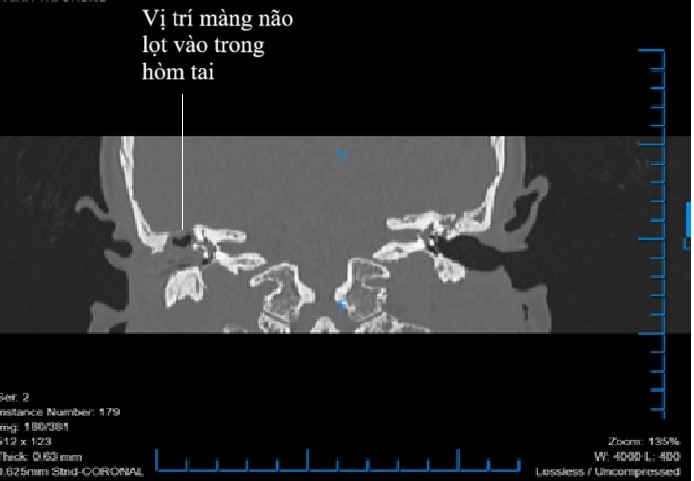

Tiếp nhận người bệnh, bác sĩ Bệnh viện đa khoa quốc tế Hải Phòng đã nhận định đây là một ca biến chứng nội sọ của viêm tai xương chũm mạn tính. Quá trình nội soi phát hiện, tai phải bệnh nhân có rất nhiều mủ chảy ra từ hộc khoét rỗng tự nhiên trong xương chũm thông ra ống tai ngoài. Hình ảnh chụp CT scanner, kết quả trên phim cho thấy xương chũm bị tiêu hủy, trần hòm nhĩ và sào bào bị ăn mòn khiến cho màng não vùng hố não giữa thông thương trực tiếp vào ổ nhiễm trùng tại tai giữa, đây chính là nguyên nhân gây ra biến chứng viêm màng não trên bệnh nhân.